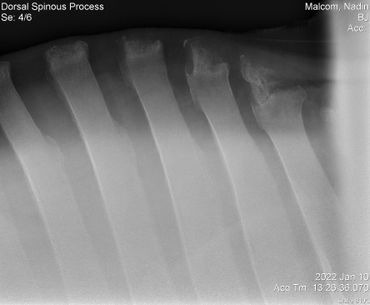

Update 03/04/2022 Billie Jean kept showing some severe sensitivity every time we touched her on her withers and along her spine so back in January we had x-rays taken to check for kissing spine. Everything looked great so we treated her for ulcers with Gastrogard paste and Sucralfate for 7 days.

Her vet bill from January 10 was $445